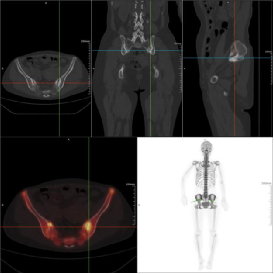

第一位患者为52岁的X女士,因长期腰部及髋关节隐痛,辗转多家医院就诊均未明确病因,疼痛反复发作影响正常生活。

(图源:科室扫描图)

PET-CT检查后,影像提示,患者左侧第4前肋局部骨质密度略减低并18F-NaF分布增高、右侧髂骨近骶髂关节处局部斑片状骨质密度增高并18F-NaF分布增高,考虑肿瘤骨转移。